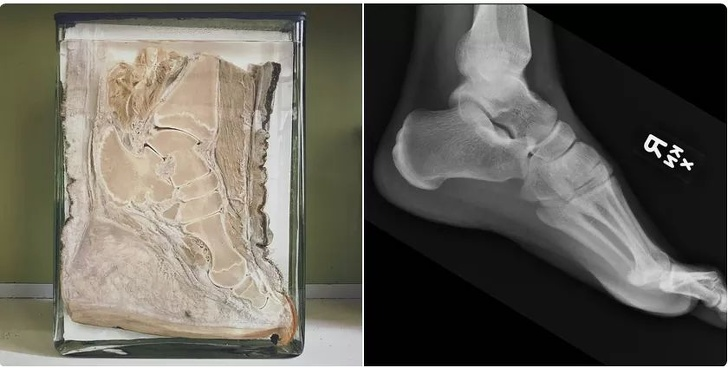

14. Hình ảnh so sánh bàn chân voi và bàn chân người.

![]() |